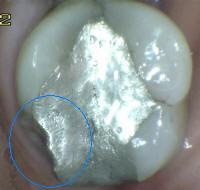

4 |

Amálgama |